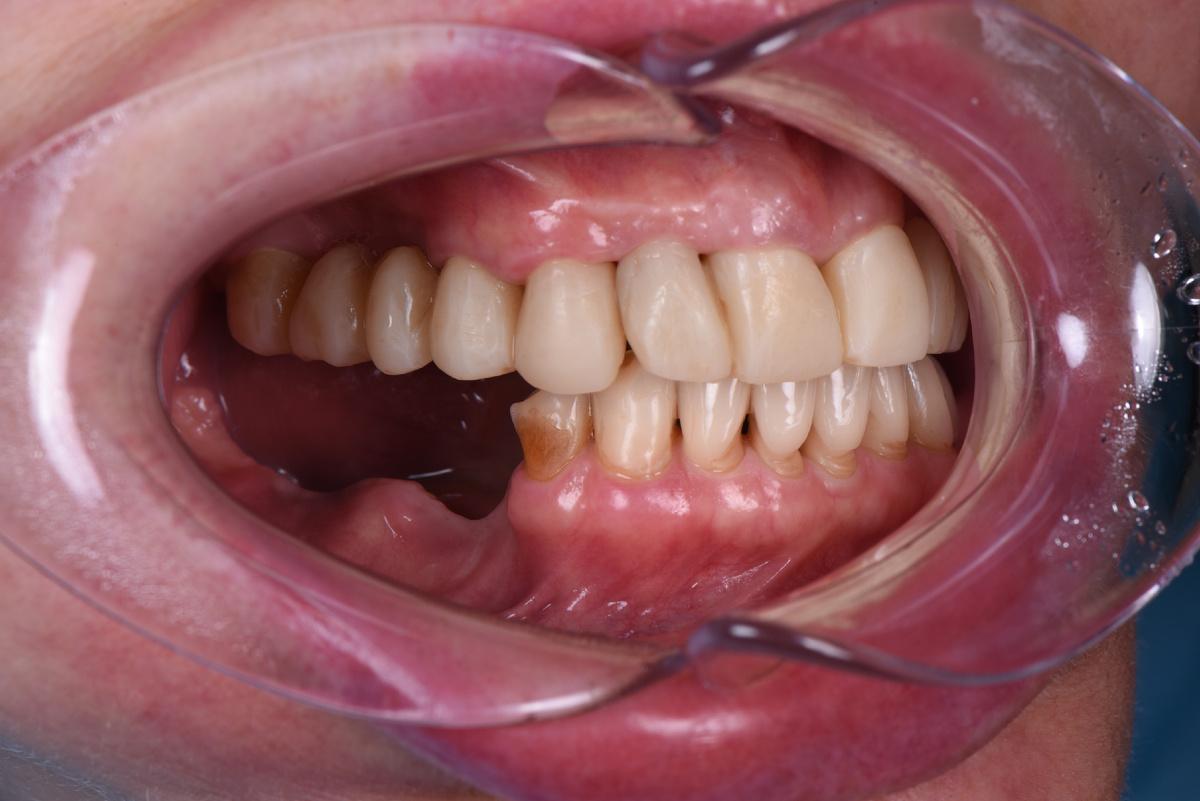

Протезирование

Оставим за скобками мероприятия по изготовлению временных конструкций, служивших не более, чем небольшим утешением нашей героине. Основная работа началась после имплантация зубов верхней челюсти, по традиции, с моделирования будущей улыбки на экране монитора (DSD)

Первая примерка :

Верхняя челюсть: 2 мостовидных протеза в жевательных отделах с опорой на 3 имплантата и мост на 6 единиц с опорой на 4 собственных зуба

Следующий шаг — коронки на нижние зубы:

Завершающий этап — после протезирования на имплантатах на нижней челюсти слева, в той области, где костная ткань восстанавливалась дольше всего